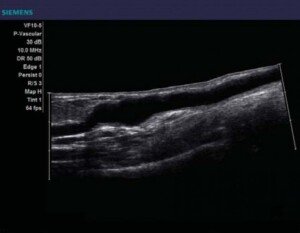

Il s’agit là d’une technique d’imagerie médicale qui vous permet de mesurer le flux d’un liquide corporel dans cas-ci le flux sanguin à travers le corps humain et ses divers vaisseaux et artères. C’est une machine grandement sophistiquée qui utilise à la perfection les différentes ondes sonores afin de déterminer de la façon la plus exacte qui soit l’emplacement des varices de manière à éliminer exclusivement les veines infectées par cette maladie !

Vous avez donc droit à un échographe classique qui est couplé d’une certaine sonde doppler qui vous est appliquée sur la peau, cet appareil spécial est à la fois un récepteur et un émetteur d’ultrasons, le flux sanguin qui est repéré sur l’image est donc possible grâce à un genre de pulsation unique qui a comme tâche d’explorer profondément la zone infectée et qui se doit d’être soigneusement étudiée afin d’établir un diagnostique parfaitement conçu !

Le doppler échographie a également la possibilité de mesurer à la perfection les grandes vitesses de flux des globules rouges au sein des vaisseaux sanguins, ce qui permet en plus de bien discerner les vaisseaux qui sont d’habitude difficilement détectables grâce à une technique qui suit de près l’écoulement du sang vers le cœur tout en visualisant au niveau du moniteur les différents mouvements liquidiens chose qui n’est pas possible avec une échographie standard.